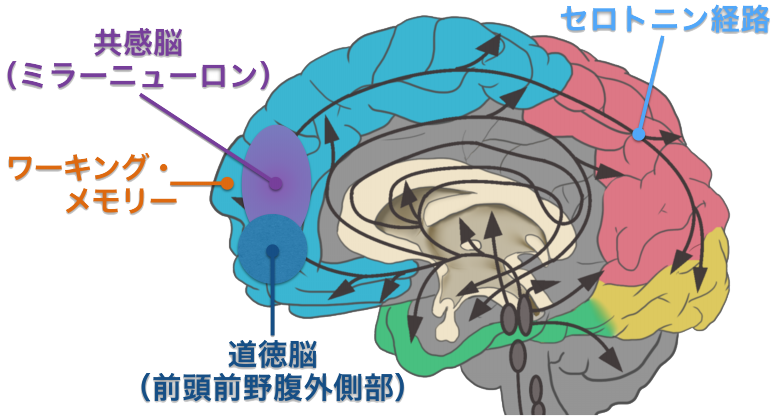

セロトニン神経系